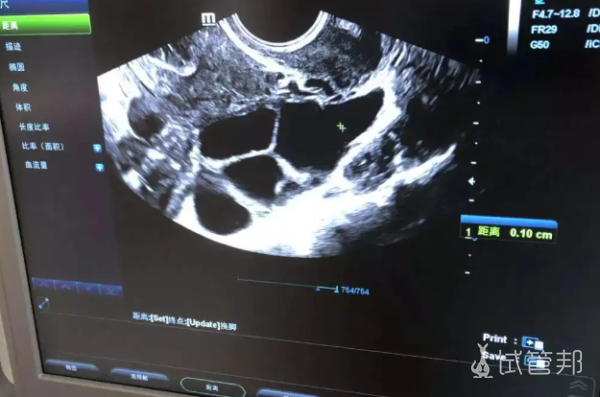

经历了前面痛苦的打针、取卵手术,我们终于到了移植这一步。我是早上8:30到医院,缴费,拿药,阴道冲洗,签字。然后喝水憋尿,建议一次不要喝太多,不然等到移植的时候再按肚子,真的很难受。我当时就感觉如果医生再用力一点按肚子,我可能就尿出来了。冷冻胚胎移植两个,整个过程挺快的,大概七八分钟就搞定了,不疼。

早上移植前,医生给我看了宝宝的第一张照片,瞬间泪流满面。因为之前的几百次注射,此刻感觉都值了,看着我的心快要融化了。